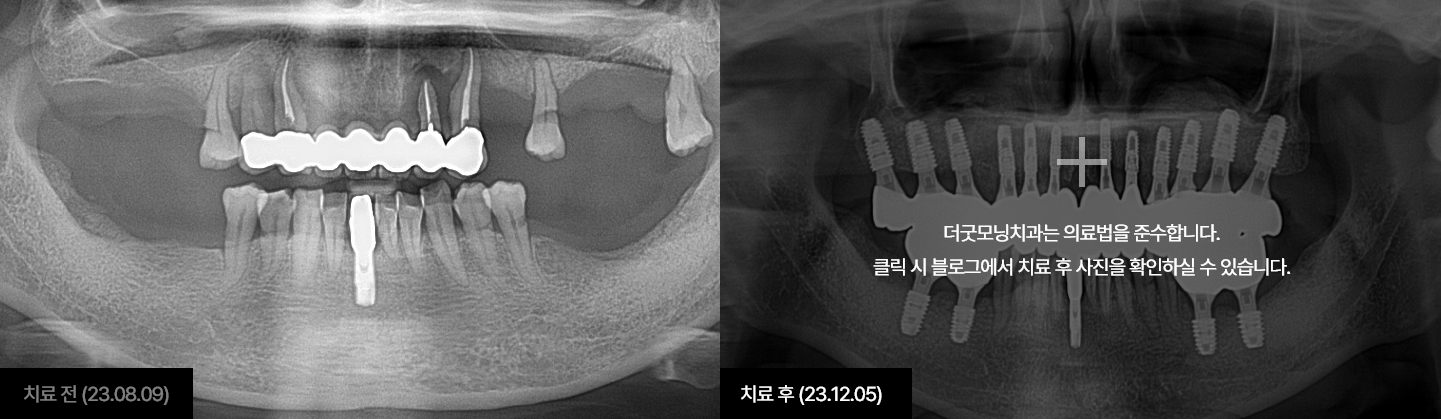

임플란트는 시술하는 의사의 수술 경험, 노하우에 따라 진료 결과가 달라지는

시술입니다.

잇몸뼈에 식립하여 자연치아를 대체해 주는 보철치료인 만큼

잇몸과

잇몸뼈에 대해 전문성이 높은 치주과 전문의가 진료해야 합니다.

더굿모닝치과는

보건복지부 인증 치주과+통합치의학과 더블보드 전문의가 직접 진료하며,

진단부터 식립, 최종 보철물까지 꼼꼼하게 완성해 드릴 것을

약속드립니다.